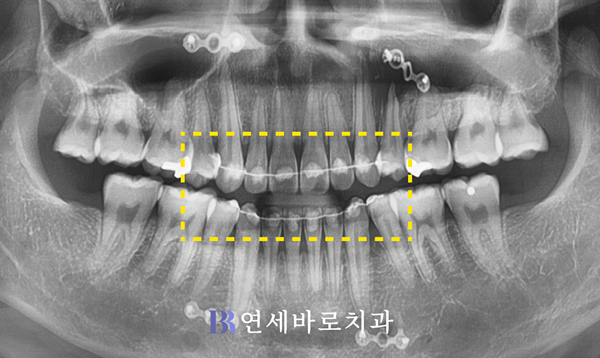

상하좌우로 제1소구치 4곳을

발치하여 공간을 만든 다음,

이곳의 뼈 일부를 절제하고

턱뼈를 뒤로 넣어주었습니다.

이것이 바로 ASO수술인데요.

여기서 유의할 점이 있습니다.

위 사진에서 윗니처럼

뿌리가 서로 벌어져 있을 때

치아와 가깝게 골절단이

가능하다고 알려졌습니다.

반대로 치근이 모아져 있으면

그만큼 수술이 어려워지는데요.

때문에 교정을 담당한 의사는

이와 같은 요소를 고려합니다.

물론 저도 이런 부분을

최대한 세심하게 반영하면서

교정치료를 진행했습니다.